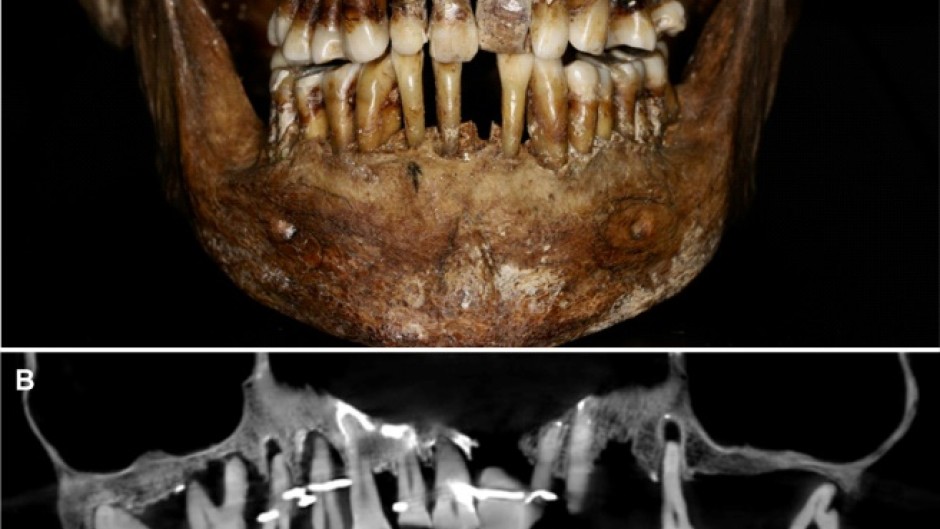

The teeth of 17th century French aristocrat Anne d'Alegre, with a gold wire threading through several

Embalmed in a lead coffin, her skeleton -- and teeth -- were remarkably well preserved.

Thirty-five years later, a team of archaeologists and dentists have identified that d'Alegre suffered from periodontal disease that was loosening her teeth, according to a study published in the Journal of Archaeological Science: Reports this week.

A "Cone Beam" scan, which uses X-rays to build three-dimensional images, showed that gold wire had been used to hold together and tighten several of her teeth.

She also had an artificial tooth made of ivory from an elephant -- not hippopotamus, which was popular at the time.